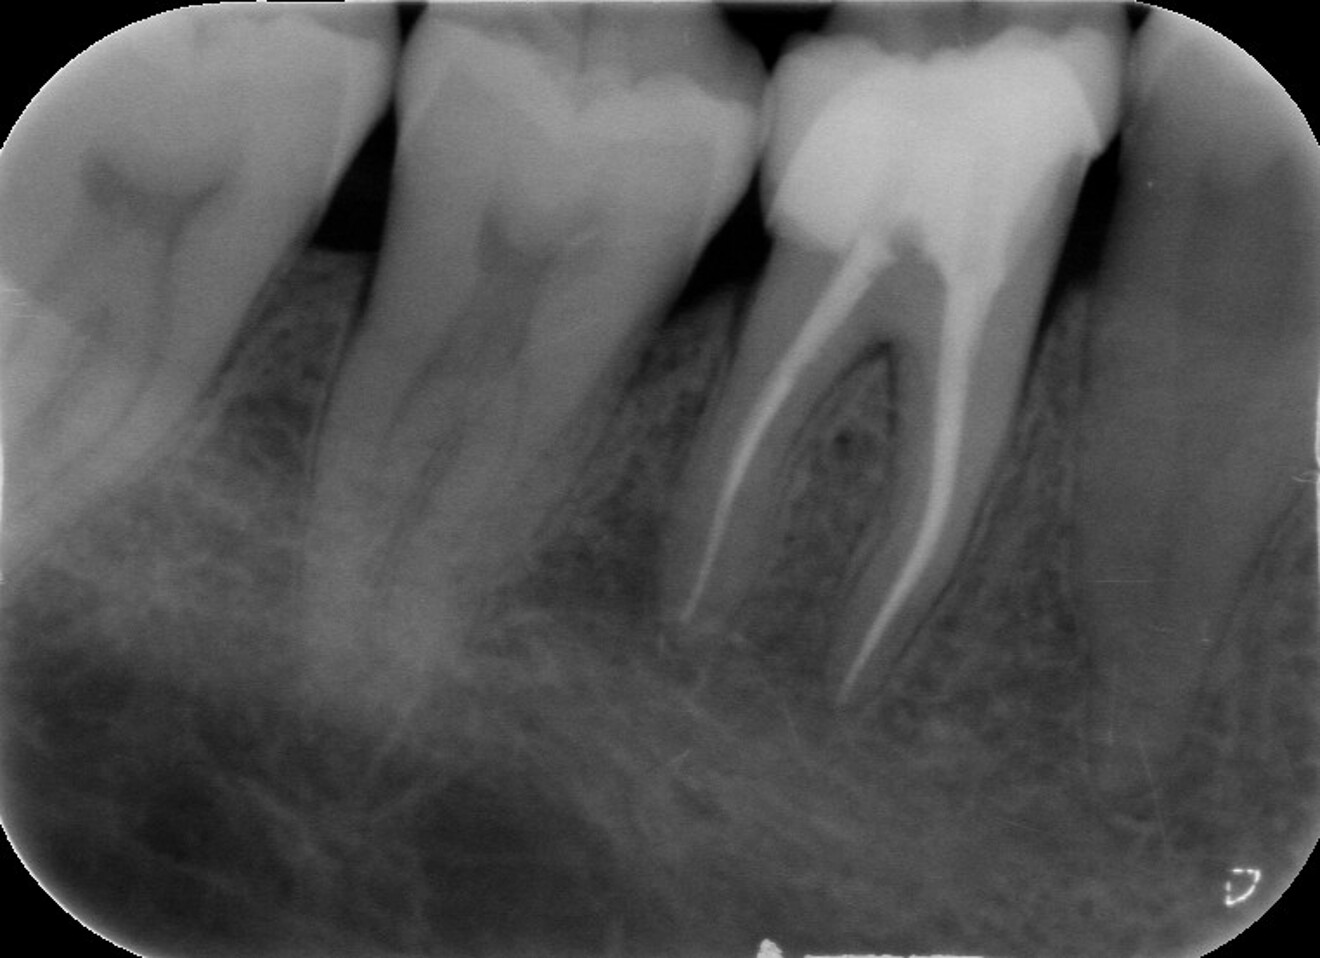

Fig. 2 : Contrôle radiographique en vue d’évaluer l’axe de délogement de la reconstitution corono-radiculaire, ce qui a permis de corriger l’angle de coupe.

D’un point de vue pratique, la première étape consiste à réduire les dimensions du tenon s’il occupe une grande partie de la structure coronaire, de préférence en lui donnant une forme cylindrique similaire à celle d’un tenon préfabriqué. De même, une reconstitution corono-radiculaire coulée ancrée dans plusieurs canaux doit d’abord être sectionnée jusqu’au niveau du plancher de la cavité pulpaire, afin de la traiter comme un ensemble de tenons unitaires, ce qui diminue le degré de rétention global du système. La réduction du tenon doit être effectuée avec des fraises en carbure spécialement conçues pour découper le métal, sous une irrigation abondante. Les évaluations cliniques et radiographies préliminaires sont essentielles pour planifier l’angle de coupe. La procédure doit être fréquemment vérifiée et, si nécessaire, il convient d’effectuer des contrôles radiographiques avant qu’une quantité excessive de dentine ne soit sacrifiée (Figs. 1–3).